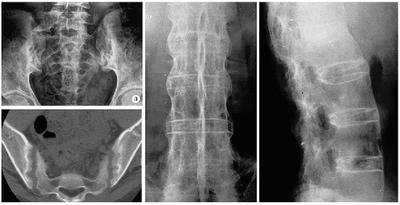

强直性脊柱炎的x线病变,最先起始于骶髂关节。随后,通常自下而上地由腰椎累及胸椎和颈椎,致使整个脊柱受到侵犯。晚期靠近椎体前缘和侧缘处,形成骨桥连接上下椎体,类似竹节状外观,故有“竹节状脊柱”之称。现在,由于医学发展,多数强直性脊柱炎患者,可得到早期诊断和早期治疗,竹节状脊柱的发生中已明显减少。